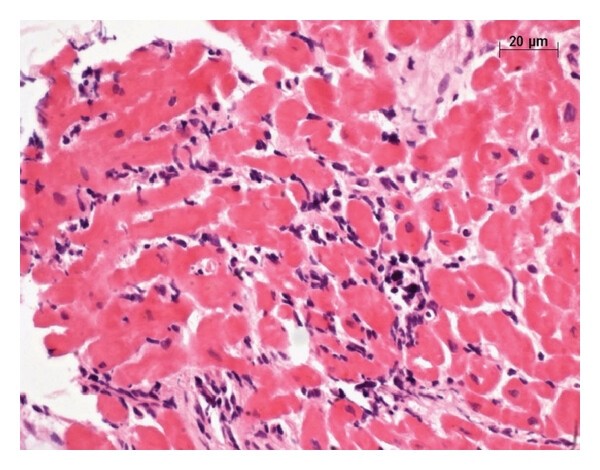

Se basa en un cuadro clínico característico (debilidad muscular simétrica, astenia, adinamia, etc.). Pueden presentarse aumento de enzimas musculares (CK muscular), alteraciones electromiográficas consistentes en ondas breves de bajo voltaje, y signos de infiltrados inflamatorios a predominio mononuclear parcheada en muestra de biopsia de músculo afectado clínicamente.